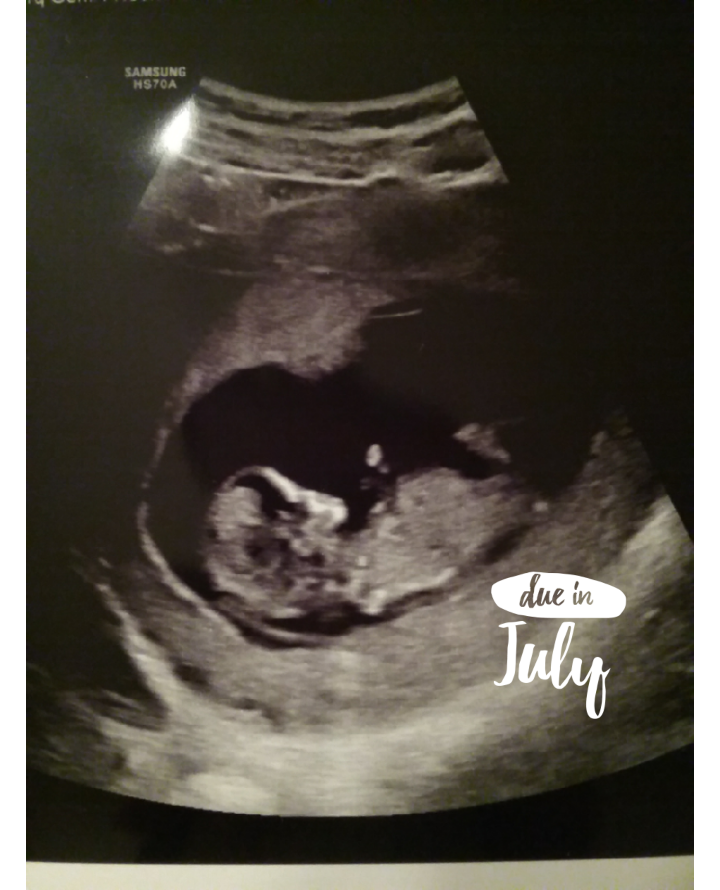

• Heres our little peanut at 7 weeks 4 days. Doesn't look like a whole lot at this point, but we were pretty excited to see the little heart beating at a rate of 152!  July 27th is our expected due date! :)